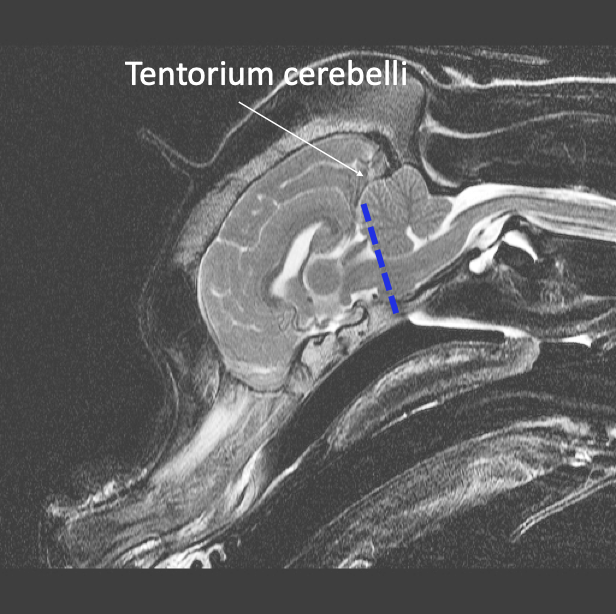

Tentorium cerebelli -

Dura that fills the transverse fissure